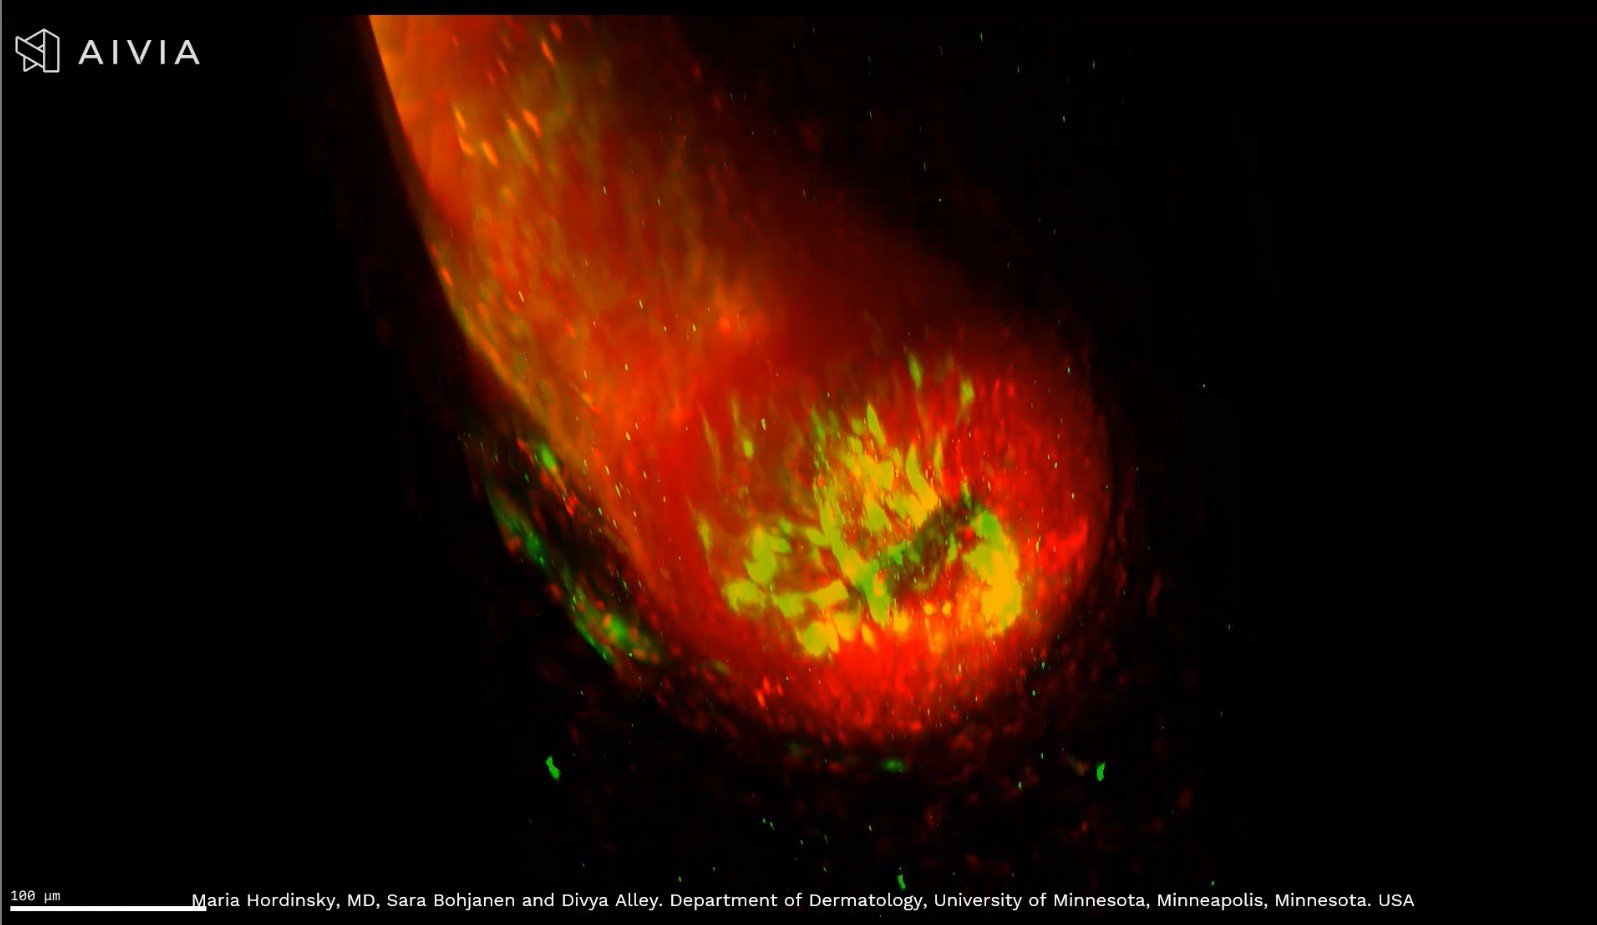

Unlocking the Secrets of Hair Follicles with 3D Imaging

See a hair follicle in stunning 3D detail, from the bulb to the dermal papilla. Using PGP9.5 and TO-PRO-3 staining, this advanced imaging highlights sensory nerve fibers and nuclei, transforming hair research and alopecia areata detection.